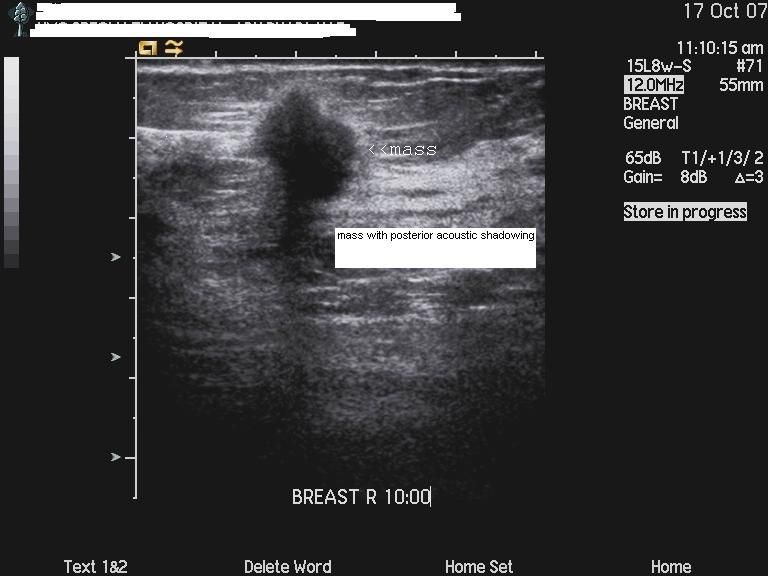

Carcinoma of breast: case-2

The above ultrasound images show a typical proven case of cancer of the left breast. The tumor is seen as a well defined hypoechoic mass with microlobulation or fine irregularities of the margins. In addition, the mass shows multiple echogenic areas along the rim a clear sign of malignancy in breast carcinoma. Images are courtesy of Ravi Kadasne, MD, UAE